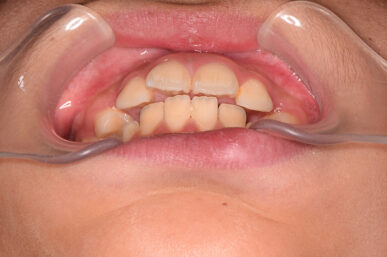

• Before

治療開始が遅くてこのままでは犬歯の生えるスペースが不足していて八重歯になるところでしたが、アライナー矯正で素早く歯を動かして犬歯が生えてくるスペースを作ることで八重歯にならずに済みました。

八重歯のケースは永久歯の抜歯が必要になることもありますが、避けることができました。

矯正後は永久歯がすべて生えるまでは予防歯科で歯の生え代わりと機能を管理します。